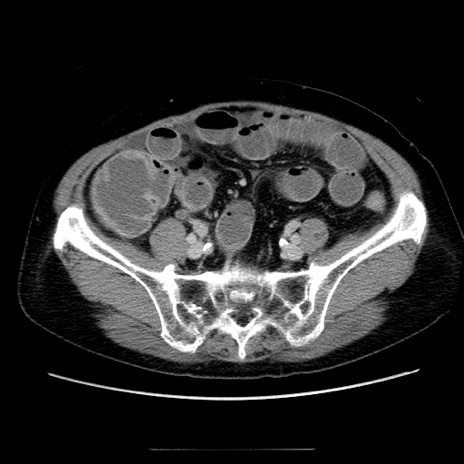

症例5(横断像)

【症例】70歳代女性

【主訴】お腹が張る

【現病歴】1週間くらい前から腹部膨満の自覚あり。昨日夜から増悪したため、本日救急外来受診。

【身体所見】意識清明、BT 36.5℃、BP 165/106mmHg、HR 80bpm、SpO2 98%、腹部:膨満、軟、自発痛・圧痛なし、触診にて不快感あり、腸蠕動音:減弱

【データ】WBC 12600、CRP 1.04